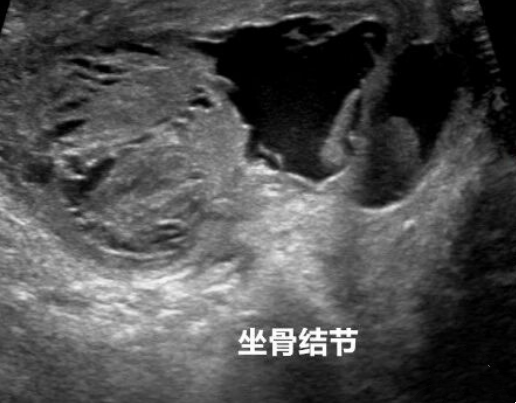

入院后,胡益华结合核磁共振检查结果,确诊左大爷臀部这两个“硬鸡蛋”为“双侧坐骨结节囊肿”。考虑到左大爷想要早出院早行走的需求,胡益华巧用关节镜微创技术摘取了困扰左大爷已久的两颗“硬鸡蛋”。

很多人以为关节镜只适用于膝盖、肩膀,其实不然。胡益华形象地解释:“这就好比用‘内窥镜’做一次精准的‘管道疏通’”。手术仅在患者臀部隐蔽处开了两个约0.5厘米的“钥匙孔”。一个孔置入高清关节镜镜头,将囊肿内部结构放大数十倍清晰地显示在屏幕上;另一个孔伸入微型刨削器和射频刀头。在清晰直视的视野下,医生巧妙避开坐骨神经,将囊肿囊壁完整剥离、清除囊内积液,并彻底止血冲洗。